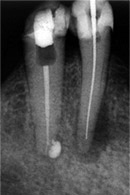

Patient(60):

Aufbissempfindlichkeit an 33 veranlasste uns erstmalig in dieser Kieferregion zu röntgen. Mit grossen Augen sahen wir dann an, was uns auch ansah. Einen Knochendefekt dieser Grössenordnung mit seiner schaurigen Aura sieht man zum Glück nicht jeden Tag. Doch, obgleich das Alien dereinst Zahn 34 entsprang, war eine Behandlung nur am Zahn davor durchsetzbar. Dessen Wurzelfüllung erfolgte regulär nach 14 Tagen, neue Terminangebote aber wurden, weil angeblich nicht mehr nötig, verschmäht.

Keine 8 Wochen gingen noch in's Land, bis das mit Macht geschah, was lange schon erwartet war. Das Arbeitsprogramm bestand aus Eröffnung von Zahn 34 und einer Schwellung inkl. Drainage, am nächsten Tag dann noch Aufbereitung des Kanals mit Einlage. 2 Wochen später dann die Füllung plus einem als Resektion deklarierten Auslöffeln des Granu­lationsgewebes durch eine Mini-Öffnung, zu deren Verschluss eine Naht genügte.

3 Aufnahmen sind von 2001, die vierte vom Nov. 2006